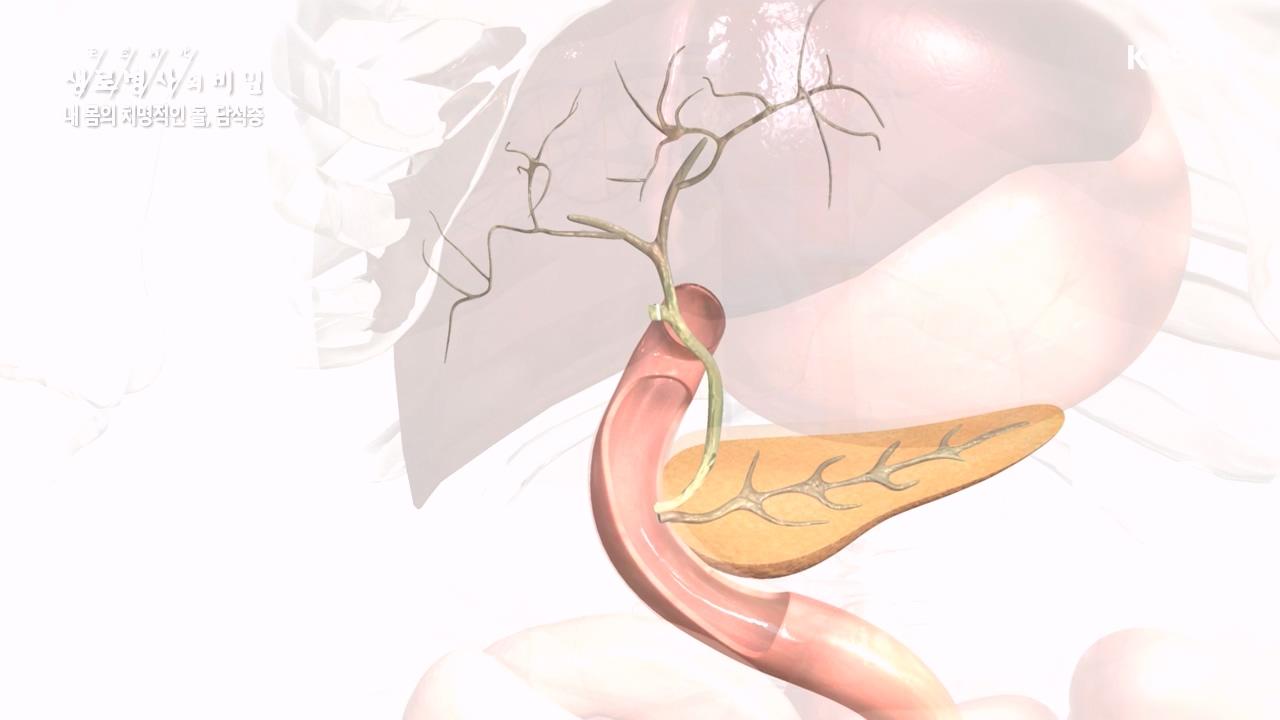

[박은철 기자] 담석증은 지방 소화를 돕는 담낭(쓸개)에 담즙이 굳어서 돌처럼 덩어리가 생기는 질환이다. 주로 쓸개주머니라 불리는 담낭 안이나...

다양한 합병증을 유발하는 몸속 시한폭탄, 담석증

내 몸의 치명적인 돌 담석증